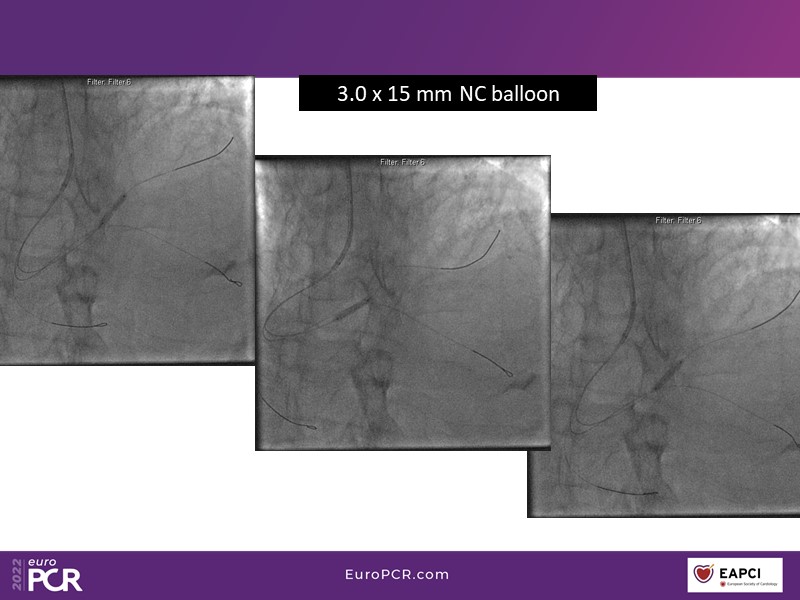

- To find out more about the application and mechanism of a sirolimus coated balloon for coronary artery disease treatment with case presentations in complex settings